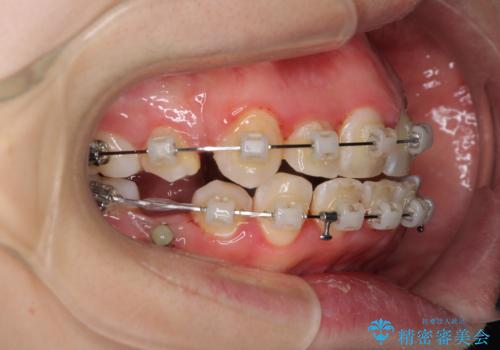

- 矯正装置

- 審美装置

治療中に舌の突出癖が改善されず、下顎前歯が著しく前方に突出して反対咬合となってしまう局面がありました。

アンカースクリューを使用しながら舌癖の改善を図り、何とか咬み合わせを改善することができました。